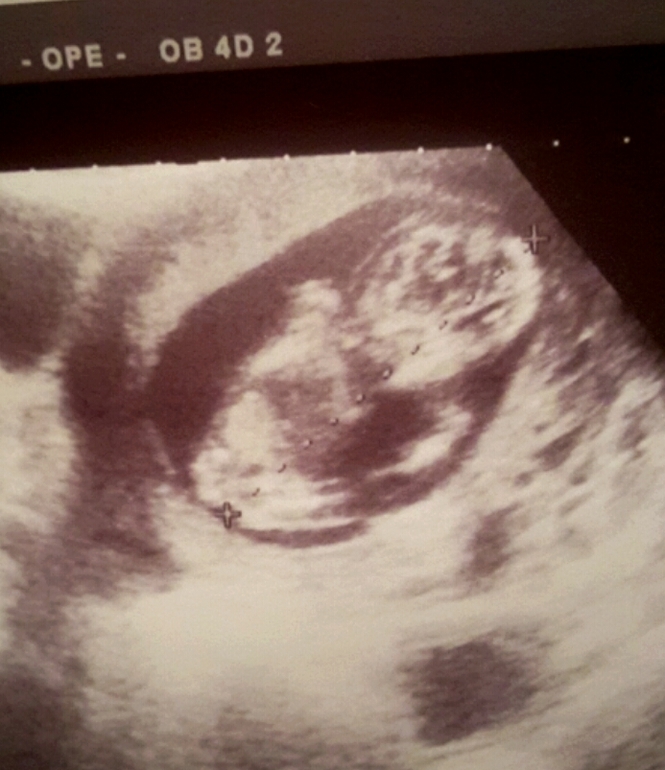

УЗИ вначале начали вагинально и ни шиша)))))говорит высоко убежал уже малш не видно толком😂потом отвели уже на кушетку через животик смотреть...аааа не могу как мило это видить❤❤❤фасолинка уже вовсе не фасолинка человечек прям такой даже боксёр какой то😂😂непоседа

Пока головку замеряли спинку позвоночник итд замер непоседа и тишина ...потом Г смеётся и говорит вот уселся как казачонок😂😂😂говорю есть причина ... дед же казах😂😂Вообщем по паспорту сегодня 13+5 по УЗИ примерно 12 недель ...всё правельно от зачатия если брать день Овуляции то знаю)))))....вообщем вотЬ наш Деть какой большой/ая знакомьтесь

тут спинкой сидит к датчику)))) стесняшка....

Кстати, очень отчетливо все на снимке видно, и глазки и ротик, и гол.мозг. Красота!!!

на плазме шикарно всё смотрелось на бумаге уже не так конечно но я и этому безумно рада)))каждый день снимочки расматриваю)))